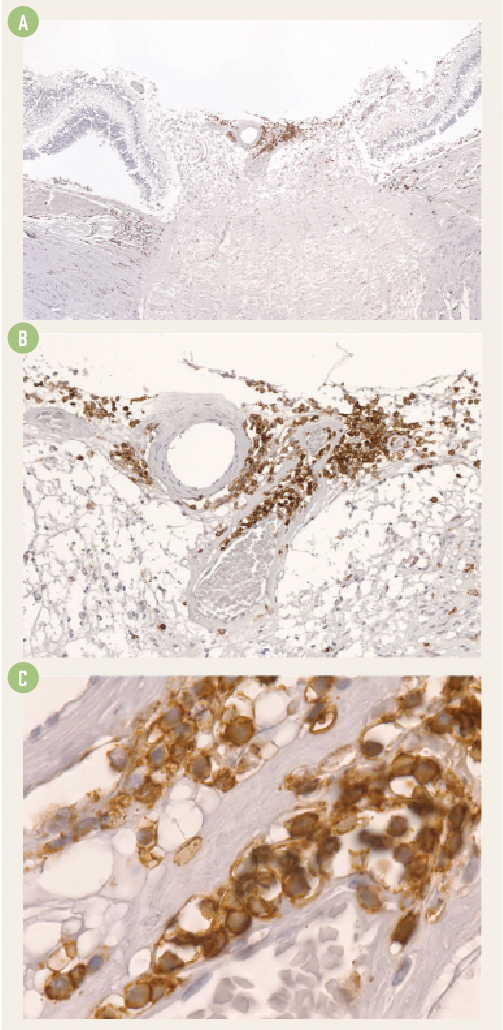

Histopathologically, focal areas of inflammation were seen in the temporal retina, presumably near the injection site, and, significantly, as an extensive angiocentric chronic lymphocytic infiltration at the optic nerve head. This correlated with the clinical intraocular infiltration.

Figure 1. Histopath slides showing the chronic angiocentric lymphocytic infiltration at low (A), medium (B) and high (C) magnification.

In patient 1, lymphocytic infiltration was observed in the temporal retina and especially around the blood vessels of the optic nerve head [Figures 1A, 1B and 1C]. AAV2-ND4 retinal transfection was evident in the injected eye and was detected at a much lower level in the contralateral eye.